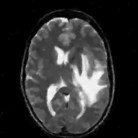

The reconstructions of a 256×256256256256\times 256 brain image from its radial samples acquired with a 40 spoke trajectory are shown in Fig. 6. The measurements are corrupted with zero mean complex Gaussian noise of standard deviation σ=18.8𝜎18.8\sigma=18.8. All methods result in loss of subtle image features since the acceleration factor and the noise level are high. We observe that the NLS scheme provides better recovery than the competing methods. The quantitative results in this setting for various MR images are shown in the bottom section of Table IV. We observe that the SNR improvement offered by NLS over the other methods are not as high as in the previous cases, mainly due to the considerable noise in the data and the high acceleration.

Figure 6: Comparison of the algorithms in the presence of noise. We consider the recovery of a 256×256256256256\times 256 original MRI brain image from its radial trajectory with 40 spokes, contaminated by Gaussian noise with standard deviation σ=18.8𝜎18.8\sigma=18.8. The error images are magnified by a scale of 5 fold for the best visibility. This is a challenging case due to the high undersampling factor and high measurement noise. We observe that the NLS scheme provides the best overall reconstructions.